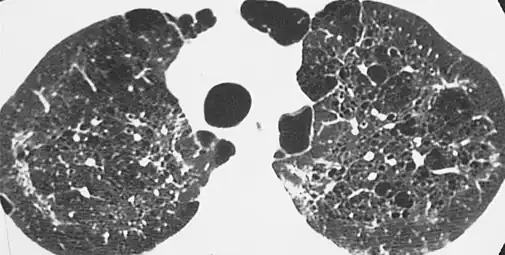

| CT scan of the lung showing bullae in the lower lung lobes of a subject with type alpha-1-antitrypsin deficiency. There is also increased lung density in areas with compression of lung tissue by the bullae. | |

A focal lung pneumatosis is an enclosed pocket of air or gas in the lung and includes blebs, bullae, pulmonary cysts, and lung cavities. Blebs and bullae can be classified by their wall thickness.[1]

- A bleb has a wall thickness of less than 1 mm.[2] By radiology definition, it is up to 1 cm in total size.[3] By pathology definition, it originates in the pleurae (rather than in the lung parenchyma).[4]

- A bulla has a wall thickness of less than 1 mm.[2] By radiology definition, it has a total size of greater than 1 cm.[3] By pathology definition, it originates in the lung parenchyma (rather than in the pleurae).[4]